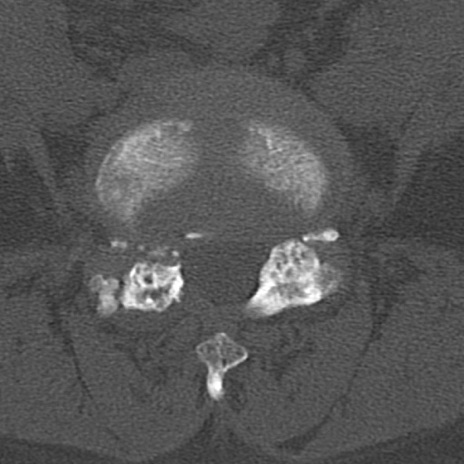

腰椎CT

横断像と矢状断像